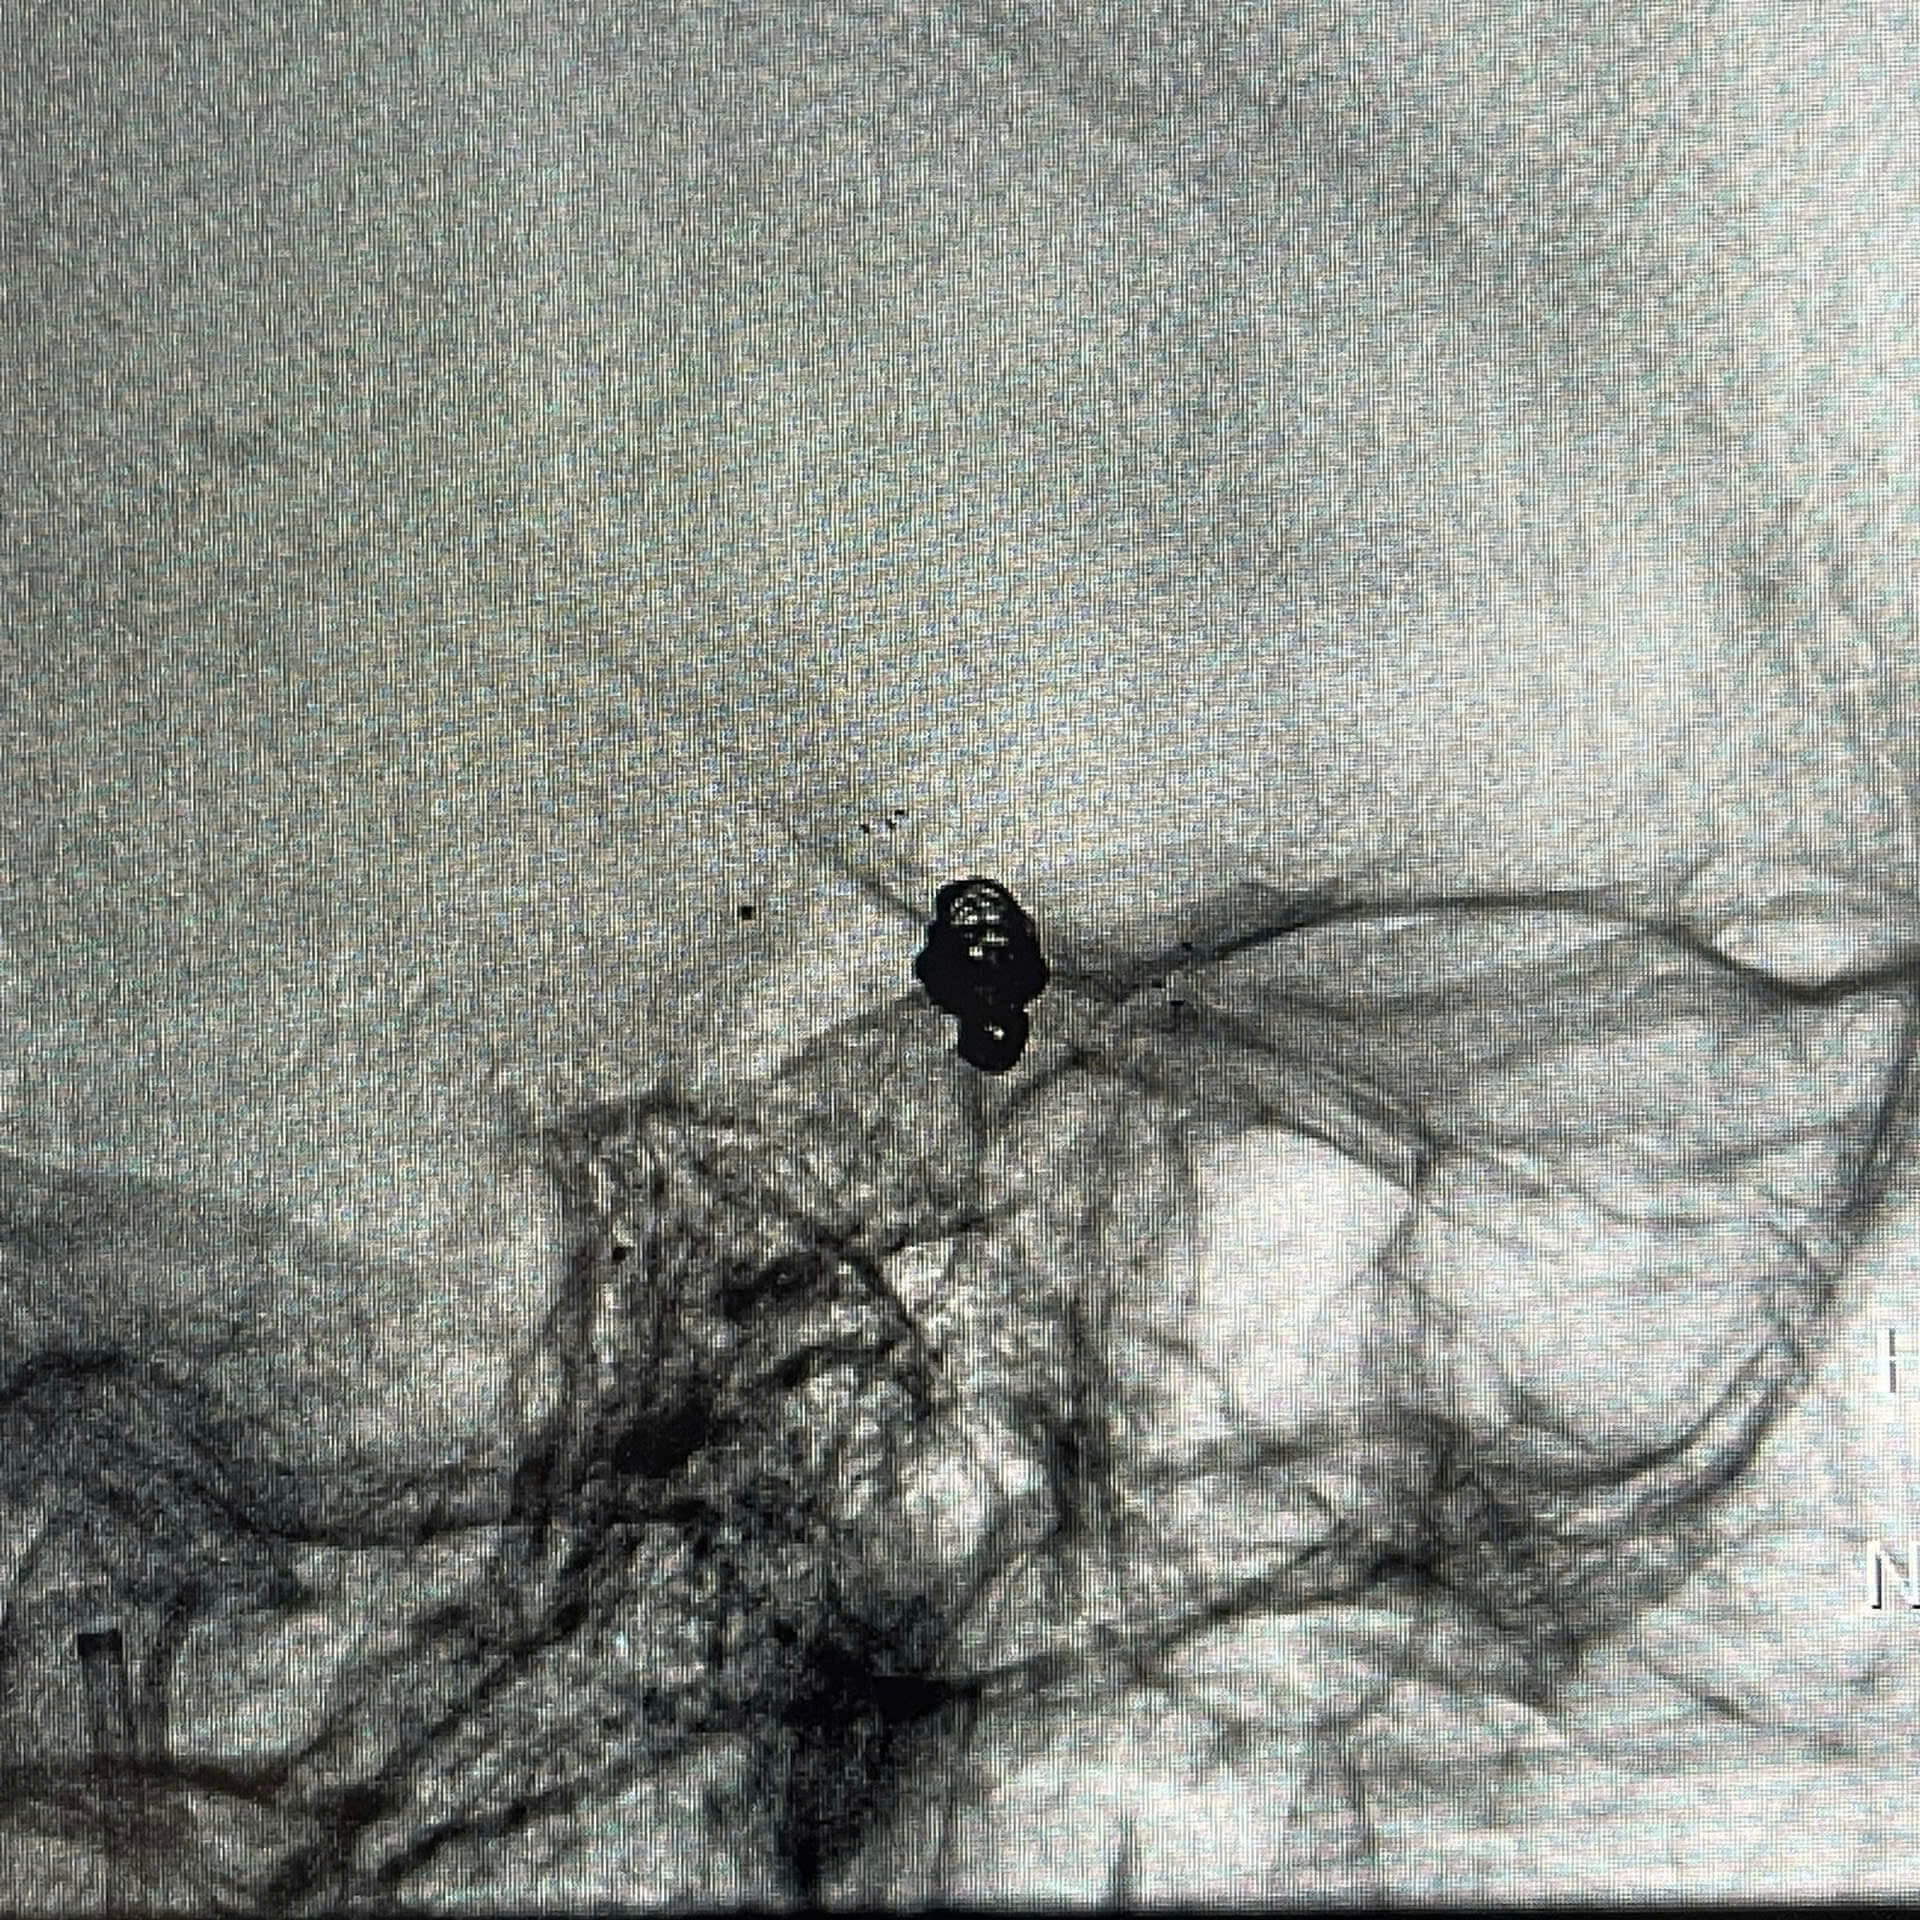

Hình ảnh DSA mạch não trước can thiệp ghi nhận túi phình động mạch thông trước

Ngay sau đó, bệnh nhân được chỉ định chụp DSA mạch não cấp cứu và tiến hành can thiệp nội mạch nút túi phình bằng coil, có hỗ trợ bằng stent nhằm loại bỏ nguy cơ chảy máu tái phát.